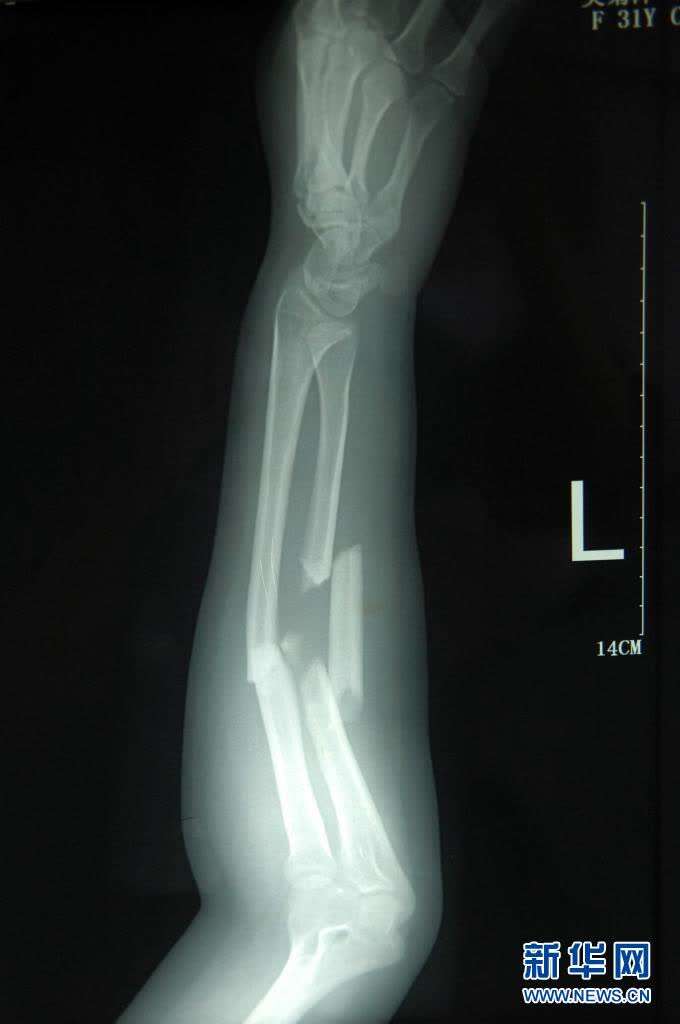

这是2011年7月3日拍摄的吴菊萍受伤左臂的X光片,医生诊断为手臂左尺桡骨多段粉碎性骨折。新华社记者 黄宗治 摄